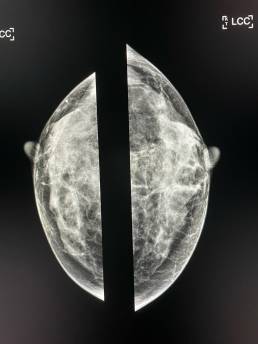

Cas de la semaine (semaine 32, 2021)

Femme de 45 , mammographie de depistage individuelle.

Mammoscreen pointe un surcroît d’opacité en projection axillaire.

L’échographie montre une formation nodulaire au contours irréguliers du quadrant supéro externe du sein droit

Carcinome infiltrant SBRII confirmé.